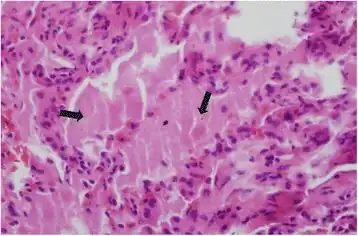

Pulmonary alveolar proteinosis high magnification photomicrograph showing complete filling of alveoli with periodic-acid-Schiff-positive granular materia

Lung washings or tissue for histopathologic analysis are most commonly obtained using bronchoalveolar lavage and/or lung biopsy.[12] Characteristic biopsy findings show filling of the alveoli (and sometimes terminal bronchioles) with an amorphous eosinophilic material, which stains strongly positive on PAS stain and the PAS diastase stain. The surrounding alveoli and pulmonary interstitium remain relatively normal.[13] Electron microscopy of the sample, although not typically performed due to impracticality, shows lamellated bodies representing surfactant.[14] An alternative diagnosis with similar histomorphologic findings is Pneumocystis jirovicii pneumonia.[14]

Lung washings characteristically yield a fluid which is "milky"composition. Under the microscope, samples show 20-50 micrometer PAS-positive globules on a background of finely granular or amorphous PAS-positive material. There is typically a low numbers of macrophages and inflammatory cells (although this is variable).[13][14]